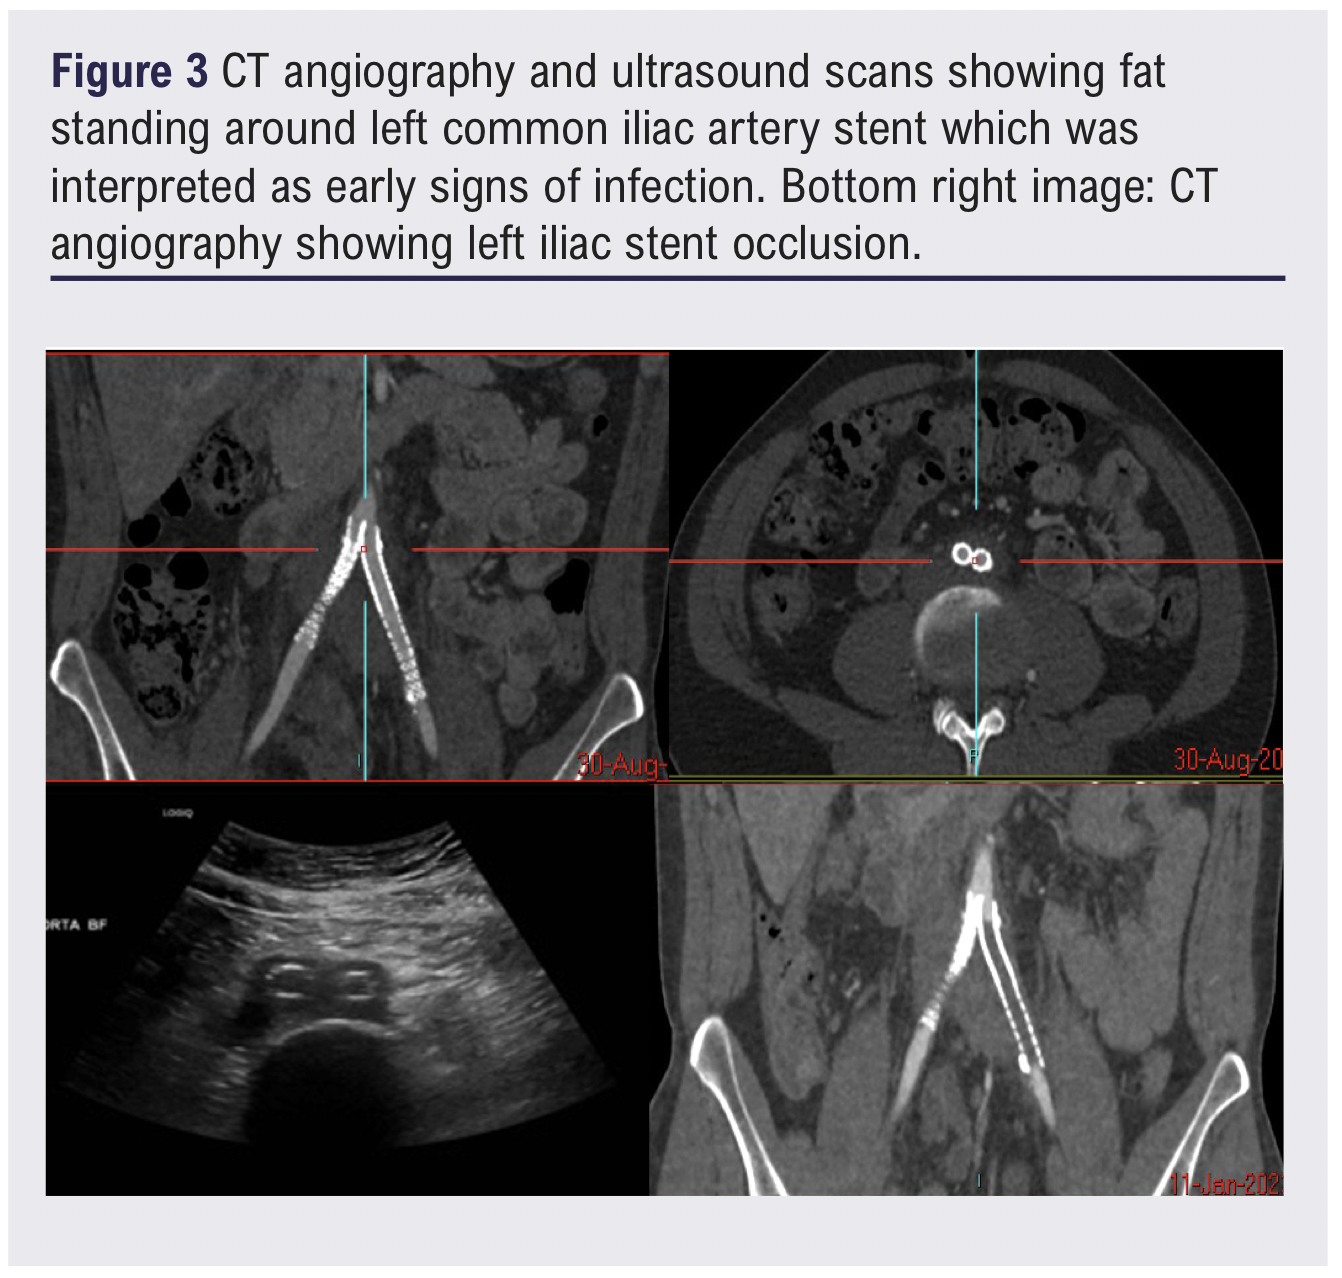

One week following the procedure the patient presented to the emergency department with mild left leg swelling and progressive unfamiliar back pain. CTA and duplex ultrasound confirmed stent patency and did not reveal any acute complications to account for the symptoms. However, fat stranding was noted around the left iliac stent and was interpreted as a potential early sign of peri-stent infection (Figure 3). A full peri-iliac stent infection work-up was initiated, including updated inflammatory markers, blood cultures, repeat CTA and a positron emission tomography-computed tomography (PET-CT) scan, which revealed occlusion of the left iliac stent.